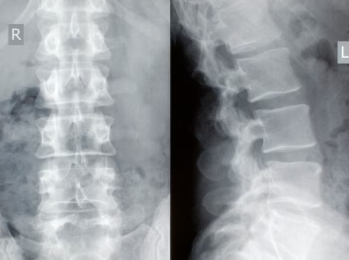

정확한 진단을 위해서는 전문 의료기관을 방문하여 방사선 검사를 진행해야 합니다. 척추 측만증의 진행 정도에 따라 치료 방향이 완전히 달라지기 때문입니다.

- X-ray 촬영: 척추의 전체적인 모양을 확인하고 휜 각도를 측정하는 '코브 각도(Cobb's angle)' 계산이 기본입니다.

- 각도 기준: 보통 10도 이상 휘어졌을 때 척추 측만증으로 진단하며, 20~40도 사이는 보조기 착용을 고려합니다.

- 추적 관찰: 성장이 끝나지 않은 환자의 경우 3~6개월 주기로 엑스레이를 찍어 척추 측만증의 진행 여부를 면밀히 관찰해야 합니다.